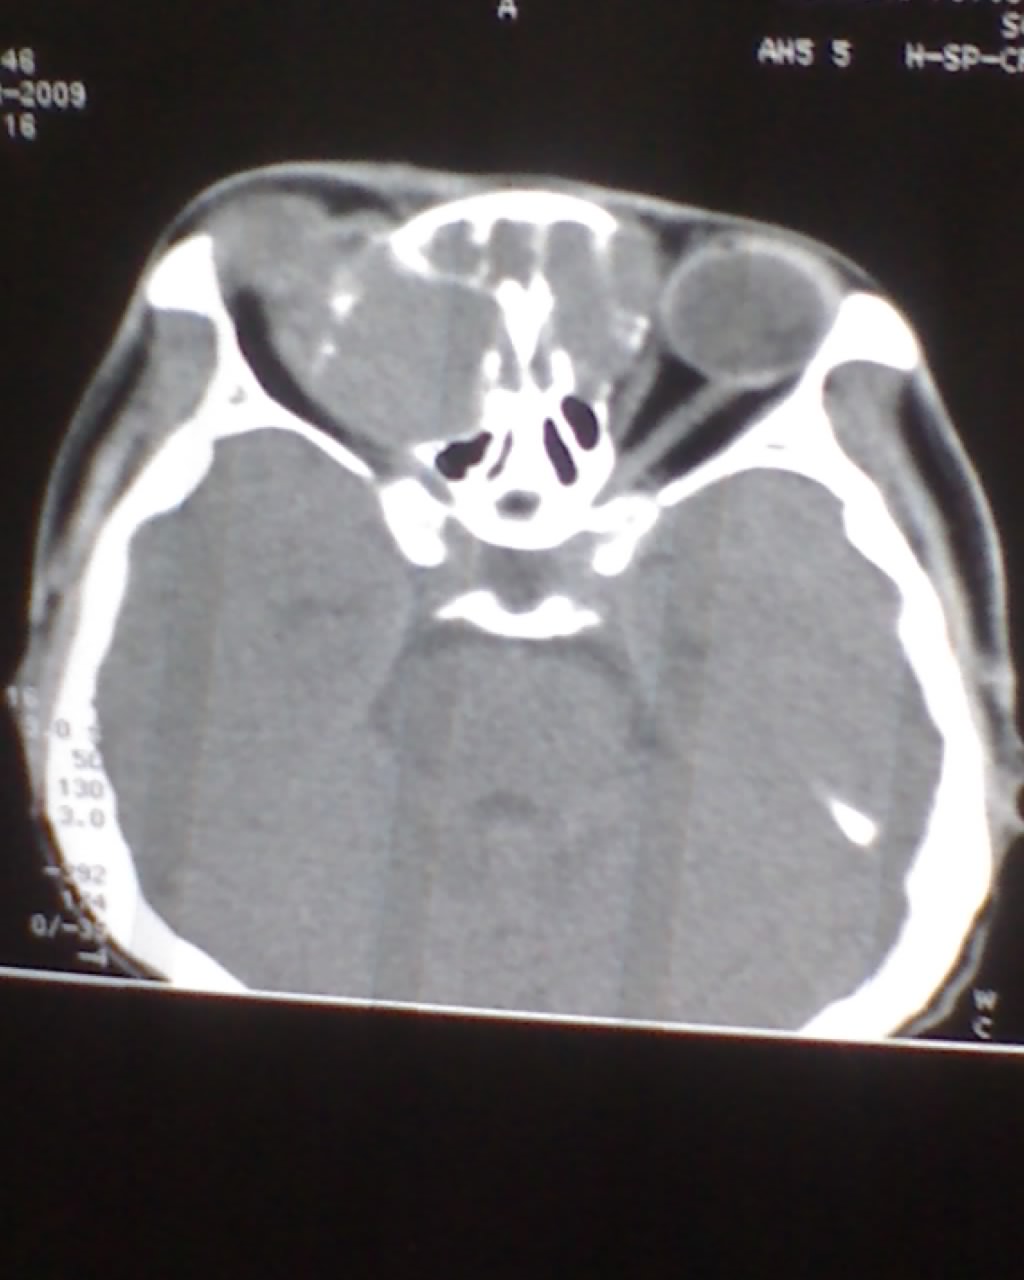

女,45岁,右眼突出,视力模糊来诊。

双侧筛窦可见软组织影充填,筛板破坏,肿块突向双侧眼眶内,以右侧为明显,右侧眼球向前外推压,右视神经稍外移。

考虑良性病变,内翻乳头状瘤可能性大,不除外息肉等。

考虑良性病变,内翻乳头状瘤可能性大,不除外息肉等。支持!(病灶明显起源于鼻窦,呈膨胀性生长,周边骨质吸收 破坏)。

双侧额窦,筛窦可见软组织影充填,筛板破坏,肿块突向双侧眼眶内,以右侧为明显,右侧眼球向前外推压,右视神经稍外移。

考虑良性病变,黏液囊肿可能性大,不除外内翻乳头状瘤等,建议强化.前者不增强.